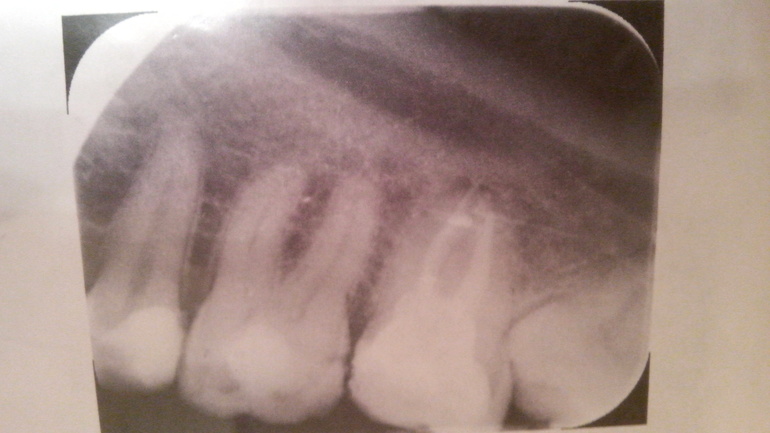

Здравствуйте ! 3года назад во время беременности нижнюю 7ку лечила у доктора,который говорил,что по всей видимости киста в нем. Но без ренгена ничего точно не сказать. Лечили закладыванием какого-то лекарства раз в месяц где -то. Еще,как помню,нерв вытаскивали. Сказали после родов лечить с рентгеном. По семейным обстоятельствам только сейчас смогла. На днях пришла к стоматологу с панорамным снимком. Доктор по снимку сомневается,что есть киста. Вскрыла зуб (тк был деффект )в зубе была вата и лекарствр в виду порошка. Каналы не запломбонированы. Врач "вытащила "нервы . было очень больно в одном месте. Запломбировала. В первые два дня все было хорошо,сегодня весь день болит. При сжимании зуба,надавливпнии,жевании. Сделала рентген новый. Снимок прилагаю. Что это может быть,киста ? Раньше эти 3года не болело.

фото прилагаю. На фото зуб второй справа